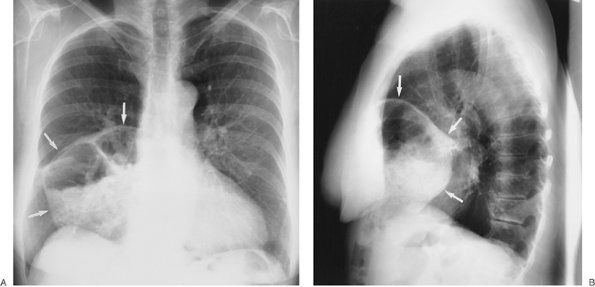

FIGURE 6-4. Morgagni hernia. PA (A) and lateral (B) chest radiographs show colon, filled with air and stool (arrows), herniating into the anterior mediastinum through a congenital defect in the anteromedial diaphragm.